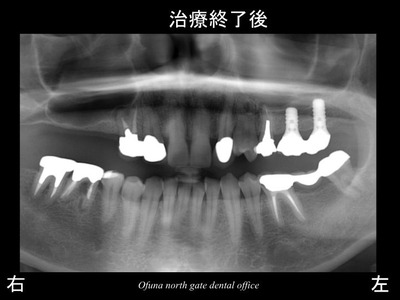

以下が被せ物を装着した後のレントゲンです。